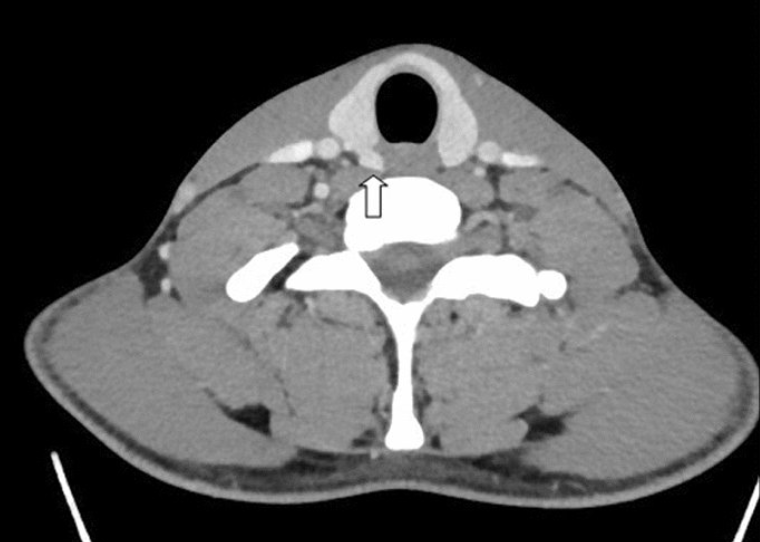

Thyroid ultrasound

A

Think hyperfunctioning (toxic) adenoma

Note: Mostly solid thyroid nodule that is hot on I-123 scan (nodule uptake with relatively suppressed background thyroid uptake).